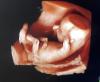

покидайте пожалуйста фотки 4d со 2скрининга 🫶🏼интересно посмотреть🥹

или 3d

щекастик🫀 🐹